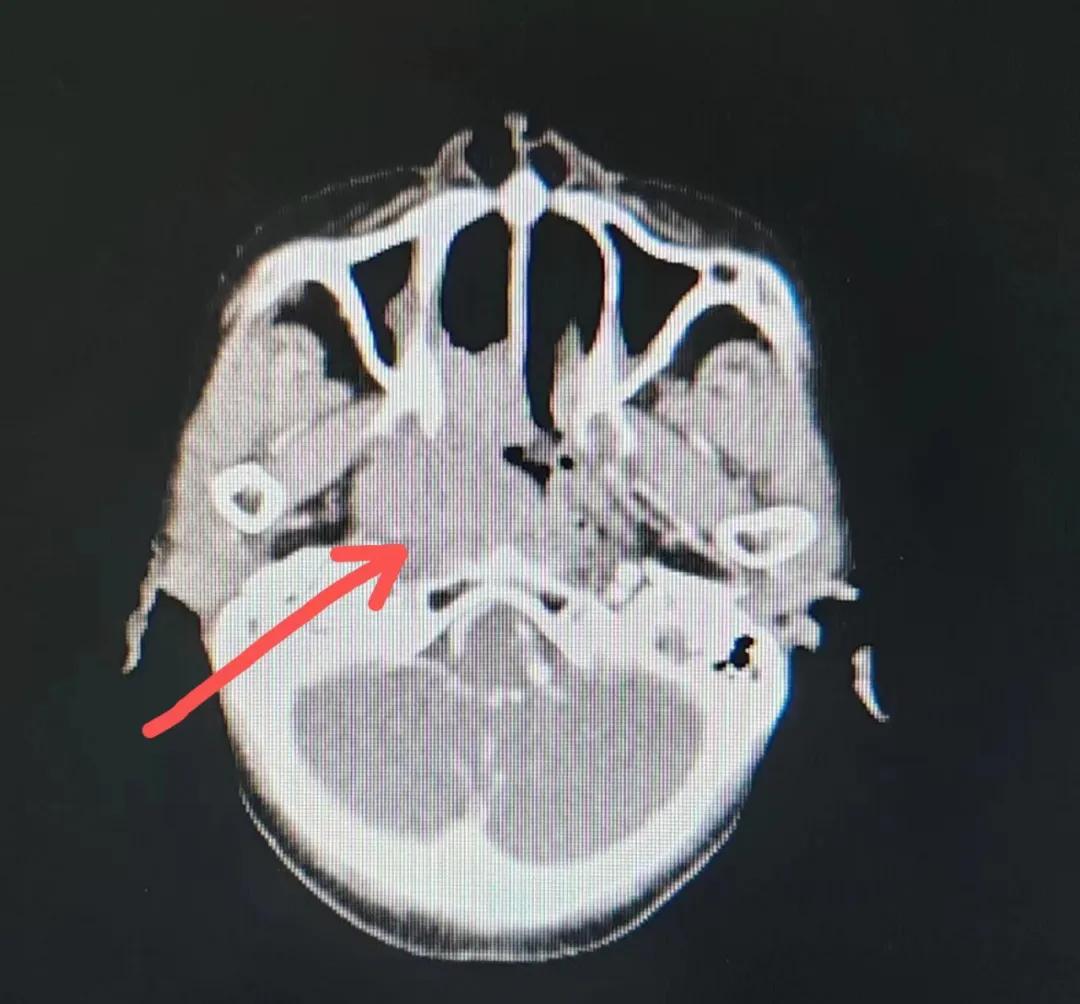

70歲的彭阿姨,5個月前因鼻部瘙癢伴流血不止在當?shù)卦\所治療,瘙癢和出血癥狀不但沒有得到有效控制,反而進行性加重,并出現(xiàn)鼻腔堵塞、進食困難,經(jīng)外院病理活檢確診為“鼻腔惡性淋巴瘤”。不斷加重的病痛已嚴重影響了老人的生活質(zhì)量,為求診治,患者及家屬于今年2月份慕名來到了市二院放療科。

治療前

老人因鼻部腫物堵塞鼻腔并且侵犯鼻咽導(dǎo)致鼻塞、疼痛、吞咽困難,身心都備受煎熬,趙亮主任在詢問其病史期間幾度落淚。趙亮主任向患者及家屬解釋說:“現(xiàn)代放療比過去的傳統(tǒng)放療設(shè)備先進,技術(shù)不斷提升,能對腫瘤區(qū)域的照射劑量進行優(yōu)化,做到準確定位、精準照射,同時,最大限度地降低正常組織的受量,對全身情況影響很小。”

考慮到患者年齡較大、體質(zhì)差,手術(shù)難度大,且常規(guī)的放射治療難以保護患者晶體造成患者雙眼視力損傷,放療團隊以最快的速度制定了精準放射治療方案并開始為其實施治療。僅僅數(shù)日后,老人腫塊出血即得到控制,腫塊明顯縮小,放療20次后腫塊迅速縮??!